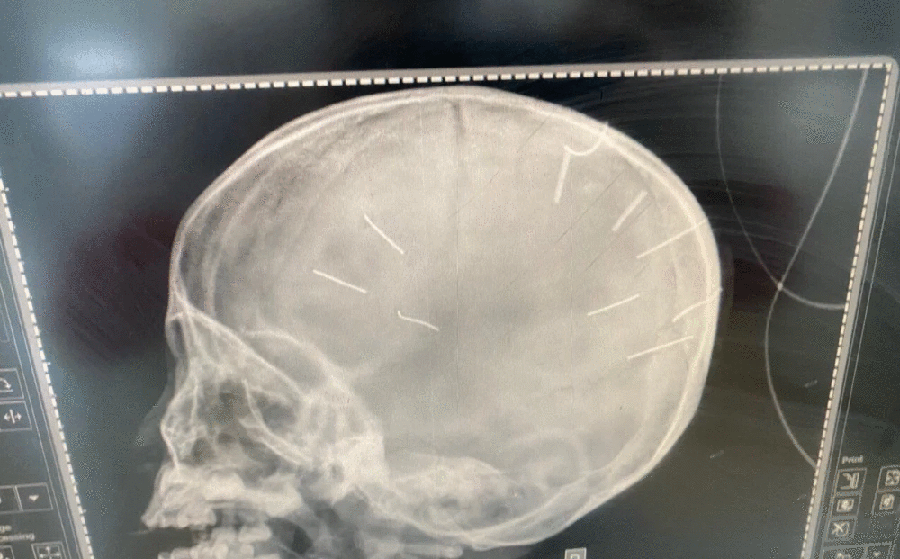

Sáng 13-3, nhiều người thân, người hàng xóm đã tới tiễn biệt bé ĐNA (3 tuổi) ở xã Canh Nậu, huyện huyện Thạch Thất, TP Hà Nội về nơi an nghỉ cuối cùng. Bé A. là nạn nhân bị người tình của mẹ ghim nhiều chiếc đinh vào đầu, dù đã được các bác sĩ tại bệnh viện Xanh Pôn tích cực cứu chữa nhưng cháu bé đã không qua khỏi sau ba tháng điều trị.

Trước đó, chiều tối 17-1, Bệnh viện Đa khoa huyện Thạch Thất tiếp nhận bé gái ĐNA, 3 tuổi, xã Canh Nậu, huyện Thạch Thất nhập viện trong tình trạng hôn mê và co giật. Bé A. được chuyển lên Bệnh viện Đa khoa Xanh Pôn, sau khi chụp chiếu phát hiện nhiều chiếc đinh trong sọ não.

Ngày 20-1, Công an TP. Hà Nội khởi tố, bắt tạm giam Nguyễn Trung Huyên, 30 tuổi, thợ mộc, là nhân tình của mẹ bé A. Tại cơ quan công an, Huyên khai nhận đã đóng đinh vào đầu bé gái.